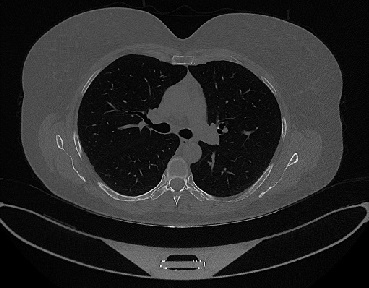

It should be mentioned that for explainability purposes [7, 8, 9], an anchor set was generated for the COV19-CT-DB database [5]. This included 11 anchors, each representing a respective 3-D CT scan obtained through an appropriate clustering procedure. Figure 2 shows a series of slices from a COVID-19 case, whereas Figure 3 shows a series of slices from a non COVID-19 case.